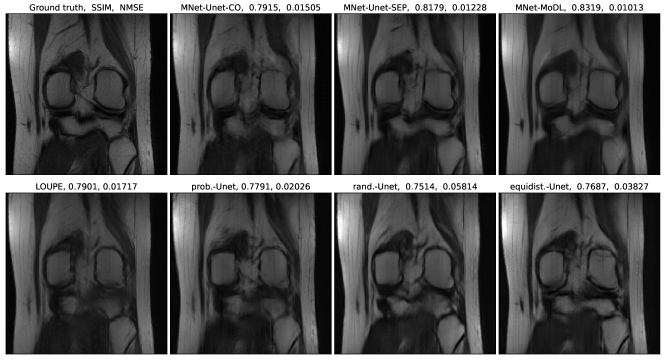

Figure 4 is an example showing the reconstructed images by several different reconstructors based on information collected from k𝑘k-space according to different masks. The different corresponding masks are shown in Figure 5. We consider the following combinations of sampler-reconstructor pairs: MNet and co-trained Unet (Unet-CO), MNet and follow-up separately-trained Unet (Unet-SEP), MNet and a follow-up separately-trained MoDL reconstructor (MNet-MoDL), LOUPE co-trained sampler and reconstructor, random sampling mask and separately-trained Unet (rand.-Unet), equi-distance mask and separately-trained Unet (equidist.-Unet), and energy density-based probabilistic mask and separately-trained Unet (prob.-Unet). We note the SSIM and NMSE values above the shown images.

Refer to caption

Figure 4: Reconstruction results from various combinations of sampler-reconstructor pairs with 8×\times acceleration of k𝑘k-space.

One should note that the adaptive MNet mask shown in Figure 5 is for the ground truth object in Figure 4, while the underlying probabilistic parametrization of LOUPE mask in Figure 5 is fixed after the training process completes with respect to the training dataset. The random mask is re-generated for each different input during the training and testing process, so the random mask used in the sampling process can differ from one object to another. The equi-distance mask is fixed with respect to the entire training and testing dataset given the pre-assigned amount of low frequencies observed and the amount of sampling budget for remaining high frequencies.